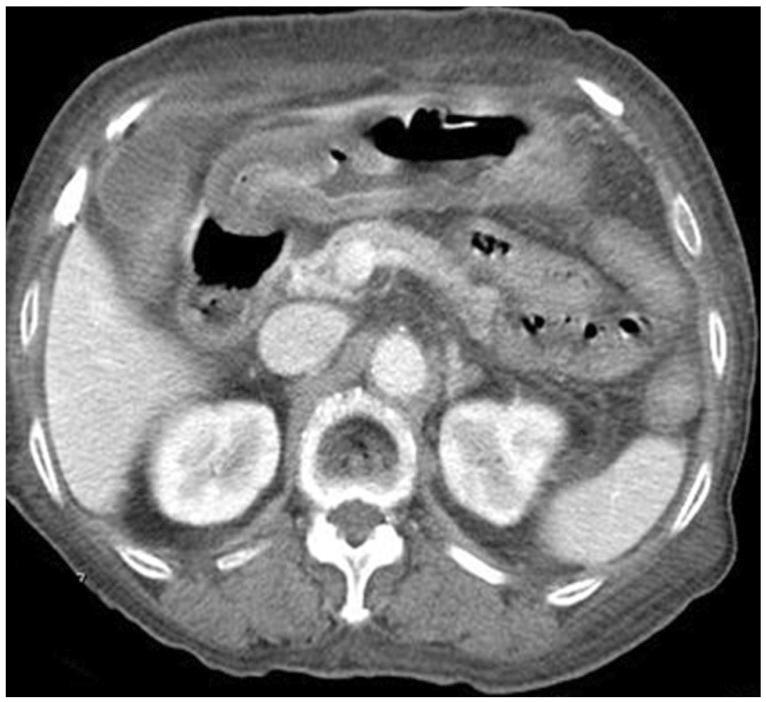

Amyloidosis is characterized by extracellular deposition of insoluble protein fibrils that stain with Congo red application and appear apple green under polarized light. The presenting symptoms result from the involvement of many affected, nonspecific and generalized organ systems. Our patient was an 80-year-old woman with no medical history. She presented with a 2-week history of nausea and vomiting. An esophagogastroduodenoscopy showed erythematous and edematous mucosa on the antrum with pyloric stenosis. Histopathologic examination of the biopsy specimen showed the deposition of amorphous, homogeneous, and acidophilic material in the gastric mucosa. Amyloidal protein was proven by positive Congo red stain. A serum and urine immunfixation electrophoresis showed lambda light chain band. She developed symptoms of repeated greenish color vomiting. A follow-up esophagogastroduodenoscopy showed progressed antral obstruction. However, she refused further evaluation and treatment and was managed conservatively. She later died of disease progression after 34 hospital days.

淀粉样变性的特征是不溶性蛋白原纤维在细胞外沉积,用刚果红染色后在偏振光下呈苹果绿色。出现的症状是由许多受影响的、非特异性的全身性器官系统受累所致。我们的患者是一位80岁的无病史女性。她有2周的恶心和呕吐病史。食管胃十二指肠镜检查显示胃窦黏膜红斑和水肿伴幽门狭窄。活检标本的组织病理学检查显示胃黏膜中有无定形、均匀、嗜酸性物质沉积。刚果红染色阳性证实为淀粉样蛋白。血清和尿液免疫固定电泳显示λ轻链带。她出现了反复绿色呕吐的症状。随访的食管胃十二指肠镜检查显示胃窦梗阻进展。然而,她拒绝进一步评估和治疗,采取了保守治疗。34个住院日后,她最终死于疾病进展。